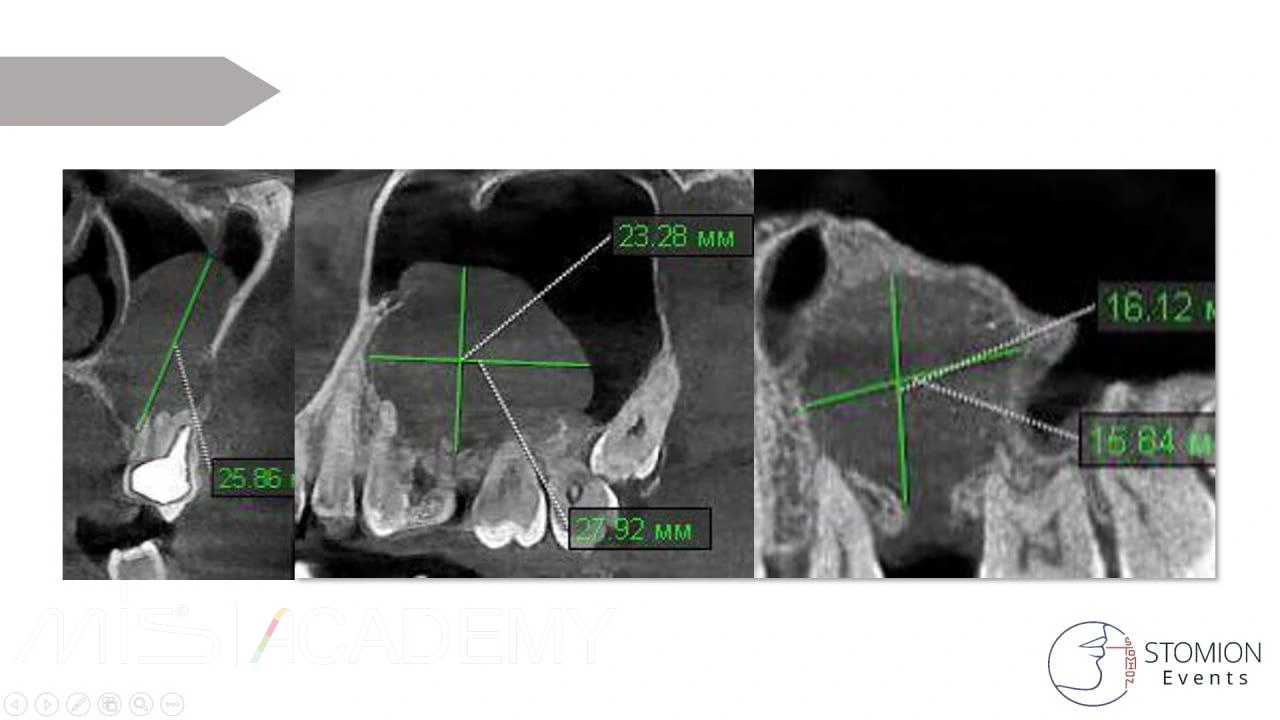

— Провели КЛКТ и анализ полученных данных. Обнаружена корневая киста примерно 26х28мм от зуба 2.5.

Что мы видим на промежуточном осмотре?

— По данным КЛКТ рентгенологический объём уменьшился, по периметру мы видим формирование нативной кости с кортикализацией.

— По цифровым данным КЛКТ отмечаются зоны до +100-300, что говорит о формировании костных балок.